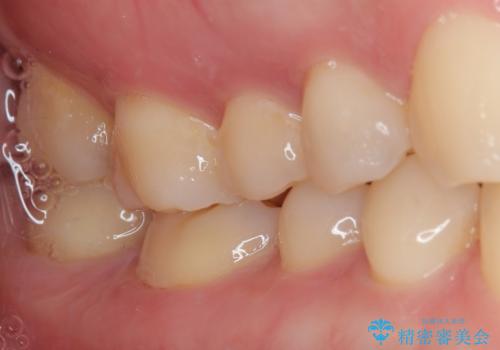

レントゲン像から、隙間のない精度の高い詰め物が入っていることが確認できます。